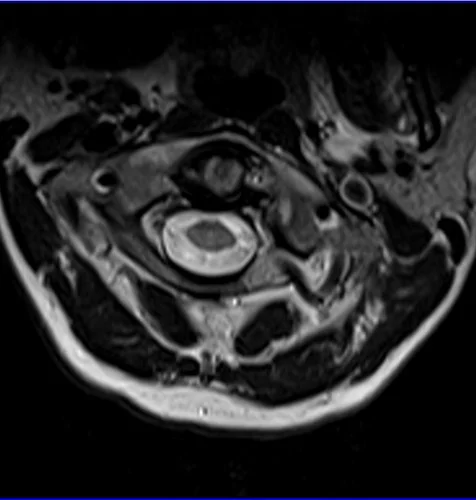

Spinal cord MRI T2 axial images of cervical cord